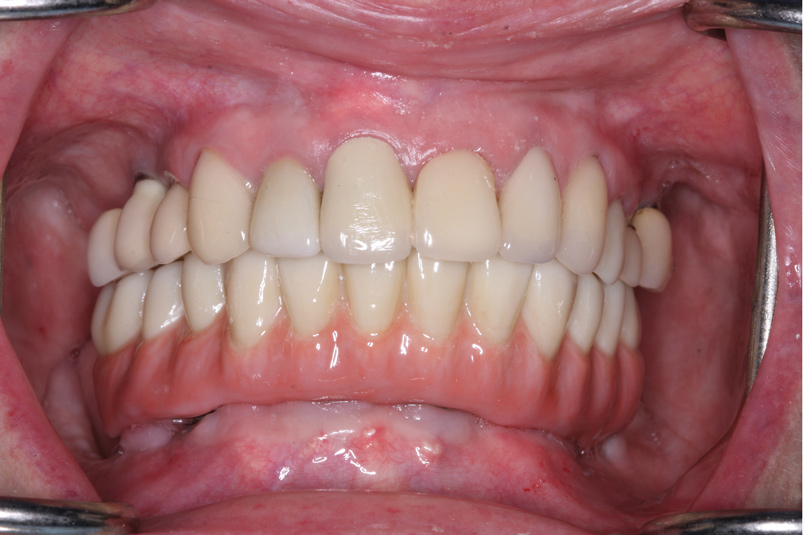

Fig 21. Postoperative close-up retracted facial view and right lateral view of the patient with her full zirconia implant-supported restoration that was salvaged using the fixed locator system.

Figure 21

Fig 22. Postoperative close-up retracted facial view and right lateral view of the patient with her full zirconia implant-supported restoration that was salvaged using the fixed locator system.

Figure 22

Delivering the Salvaged Full Zirconia Prosthesis

The retrofitted and salvaged full zirconia prosthesis was then reseated; proper and full seating of the green retentive ball was confirmed by an audible clicking sound. The prosthesis was then secured to the screw-retained abutments. The screw access holes were then sealed using polytetrafluoroethylene tape and either pink (eg, in gingival areas) or tooth-colored (eg, premolar area) acrylic material (Figure 21 and Figure 22). Considering the patient's aggressive grinding habit, her occlusal night guard was adjusted to ensure a correct fit to the new prosthesis.